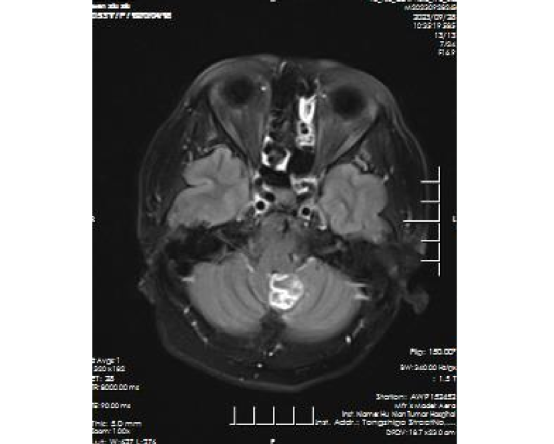

软脑膜MR平扫+增强+功能成像(DWI):小脑蚓部环状强化灶,考虑转移瘤可能性大。

△2023年9月头颅MR左小脑半球转移灶